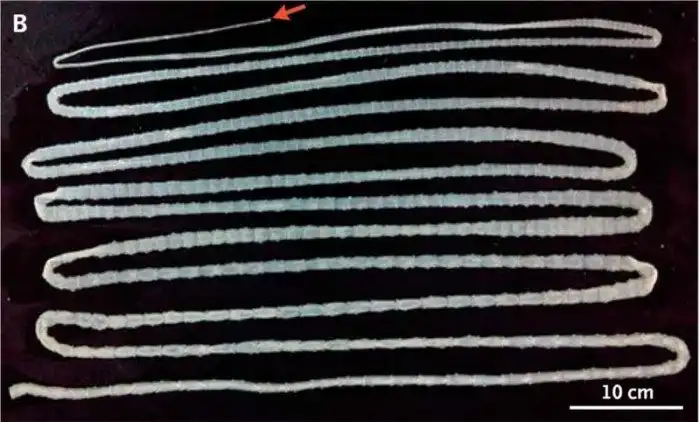

Ленточные черви

Длина ленточных червей, живущих в теле человека, может достигать 10 метров. Один из наиболее крупных представителей - бычий цепень. Случаев обнаружения - множество, но для справки: заразиться можно при употреблении в пищу недостаточно обработанной говядины.